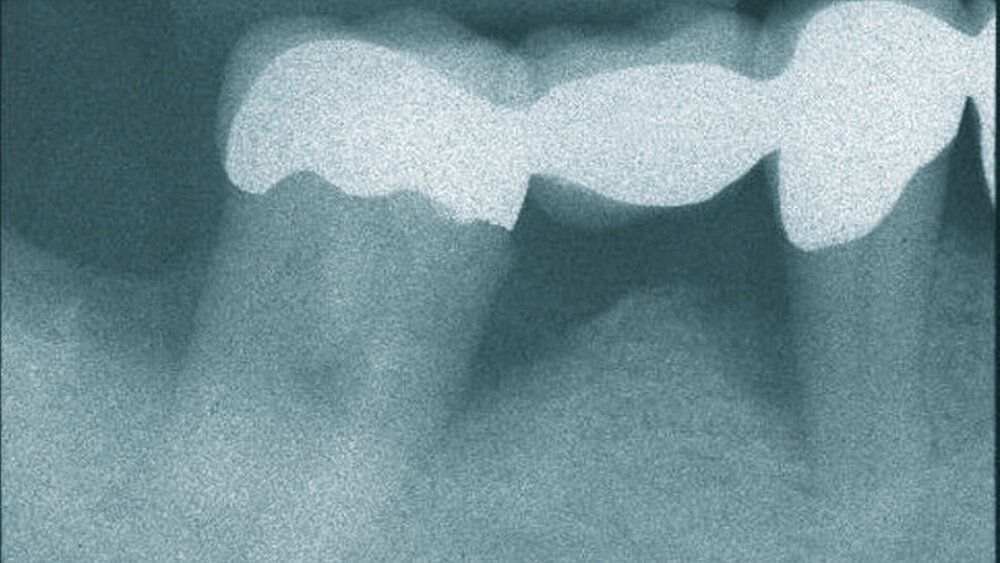

Die nichtchirurgische PA-Therapie bietet nur bis zu bestimmten Sondierungstiefen Vorteile. Der „Cut-off“ liege bei Sondierungstiefen ab 5,5 mm, sagt Stefano Tugulu, Experte für regenerative Produkte bei Straumann, Basel. Bei „noch tieferen Taschen“ plädiert er für chirurgische Maßnahmen. Doch dann drohen natürlich „die gefürchteten langen Zähne“.

Dazu Fickl: „Bei parodontitisbedingtem Attachmentverlust handelt es sich um vertikale Gewebsschrumpfungen, die sich auf chirurgischem Weg nicht korrigieren lassen“, auch nicht mit regenerativen Maßnahmen. Ziel der modernen Parodontaltherapie müsse deshalb ein sehr genaues Abwägen von offener und geschlossener PA-Therapie sein. Das gelte insbesondere für die Oberkieferfront.

Denn selbst bei feinstem mikrochirurgischem Vorgehen sei mit circa 0,7 mm an postoperativer Schrumpfung zu rechnen - und das zusätzlich zur oben genannten Schrumpfung nach nichtchirurgischer Therapie. Regenerative Maßnahmen ergeben aber Sinn, „wenn schwerwiegende Defekte des Zahnhalteapparats erkennbar sind, und der Patient neben der antiinfektiösen Therapie den ästhetischen und funktionellen Aspekt des künftigen Behandlungsergebnisses berücksichtigt wissen möchte“. Darauf weist Dr. Frank Bröseler hin.

„Die Parodontitisbehandlung folgt einem Stufenkonzept“, sagt Fickl, „zuerst konservativ, dann chirurgisch.“ Sind tatsächlich chirurgische Maßnahmen indiziert, hängt das weitere Vorgehen von der Defektkonfiguration ab: Bei vertikalen Defekten plädiert Fickl für eine Regeneration mit GTR-Verfahren, bei horizontalen setzt er resektive Verfahren oder einfache Lappenoperationen ein.